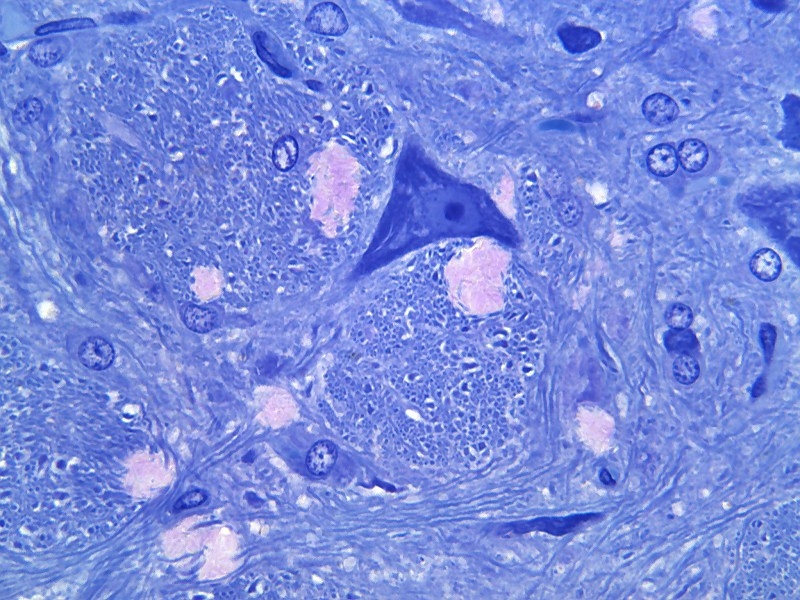

Ich denke das das gezeigte Bild ein Neuron sein könnte wie hier im gezeichnetes Bild. In dein Bild könnte 'B' dann den Kern sein.

In mein Ratten-gehirn sehe ich links und unten von das Neuron quergeschnittene Axone und Dendriten (im Negativ-Bild noch besser zu erkennen).

Das könnte natürlich sehr gut deine stelle 'A' sein.

Stelle 'C' in dein Bild könnte den Axonhügel sein aber ich meine da welches 'Raues Endoplasmatisches Retikulum' zu erkennen und das musste im Axonhügel eigentlich nicht da sein.

Siehe meine Kresylecht-Färbung.

Pfeil A zeigt eindeutig auf einen myelinisierten Axonquerschnitt. Da A und die Struktur im Rechteck abschnitte des selben Zellfortsatzes sein sollen, muss C folglich der Axonhügel sein. Differentialdiagnostisch kann man den zwar auch für sich genommen erkennen, aber definitiv nicht in dieser Kombination von niedriger Bildauflösung und geringer Vergrößerung.

Kriterien zum Erkennen von Axonen im EM Bild sind die folgenden:

- Fehlen von Nissl Substanz (insbesondere: raues ER, Ribosomen) => CAVE kann jedoch im Axonhügel noch vorhanden sein (s. Antwortmöglichkeit B)

- konstanter Durchmesser, idR. geringer als der von dendritischen Segmenten. An Verzweigungspunkten ist der Durchmesser der Tochtersegmente gleich dem des Stammes, im Gegensatz dazu sind Dendriten höherer Verzweigungsgeneration immer dünner als der Stamm.

- Verzweigungspunkte zeigen idR. stumpfere Winkel als dendritische Verzweigungsstellen.

- Die Oberfläche erscheint im Regefall glatt und ist regelmäßiger als die von dendritischen Abschnitten. Außnahme bilden gelegentliche Auftreibungen (Varikositäten) und die Axonterminalen, diese sind allerdings idR. an dem Vorhandensein von synaptischen Vesikeln eindeutig zu erkennen (Cave: diese können auch außerhalb der Schnittebene liegen)

- Das Vorhandensein einer Myelinscheide. Aber Achtung, viele Axone im ZNS sind nicht myelinisiert.

- Das Fehlen von postsynaptischen Spezialisierungen (postsynaptic densities) in Opposition zu Axonterminalen. Außnahme bildet hierbei das Axoninitialsegment, dass häufig hemmende (symmetrische, Gray II) synaptische Eingänge von Axo-axonischen Zellen empfängt. Diese jedoch direkt am Axoninitialsegment und nicht an postsynaptischen Spezialisierungen (thornes oder spines).

(Die drei letztgenannten Kriterien (Myelinscheide, synaptische Vesikel im Abschnitt, PSD) sind im allgemeinen als eindeutig anzusehen. Außnahmen sind sehr selten und kommen nur in wenigen Abschnitten des ZNS vor.)

Proteinsynthese ist definitiv keine Funktion des Axons, kann jedoch zumindest im Axonhügel gelegentlich vorkommen. Bei E müsste man wissen, was genau hier mit dem Begriff "Dornen" gemeint sein soll. Neuronale Abschnitte zeigen viele Arten von Frotsätzen (z.B. (echte) spines, thornes, filopodial extensions (letztere sowohl als Adnex am Dendriten, als auch als sonderform von Präsynaptischen Terminals, z.B. bei Moosfasern des Gyrus Dentatus). Den deutschen Begriff "Dornen" hätte ich intuitiv mit "spines" übersetzt, damit wäre E definitiv weniger wahrscheinlich als B (weder Axone noch Axonhügel empfangen nach derzeitigem Kenntnisstand Synapsen an Spines). Bezieht sich der Begriff jedoch auch auf andere Formen von kurzen neuronalen Fortsätzen wäre B die richtige Antwort.